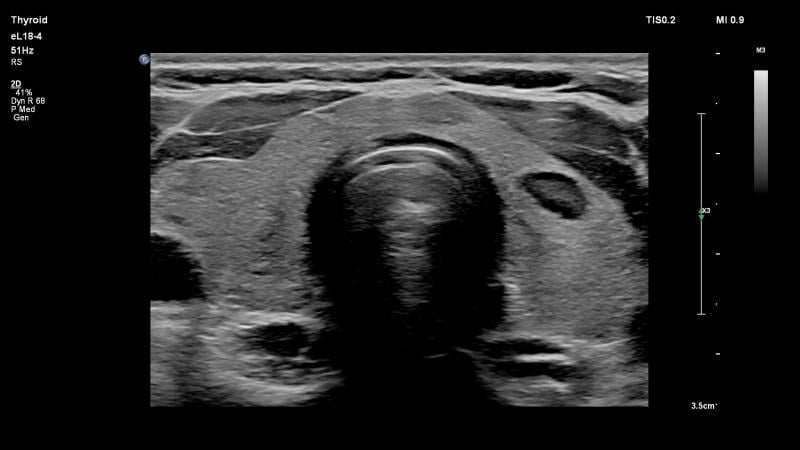

October 17, 2017 — Philips announced it has received 510(k) clearance from the U.S. Food and Drug Administration (FDA) to market the new eL18-4 transducer with full solution for 'small parts' assessment. These ultrasound exams detect abnormalities in the small organs that are close to the skin. The Philips Ultimate Small Parts Solution features four key innovations that work together to help improve patient care: the eL18-4 PureWave linear array transducer, Philips MicroFlow Imaging, Philips Elastography and Philips Precision Biopsy. The new eL18-4 transducer can also be used to assess musculoskeletal injuries.

- The Philips eL18-4 transducer allows fine-elevation focusing to deliver exceptional detail resolution and tissue uniformity for clinical solutions, including: thyroid, breast, testicular, musculoskeletal, vascular, bowel, pediatrics and obstetrics;